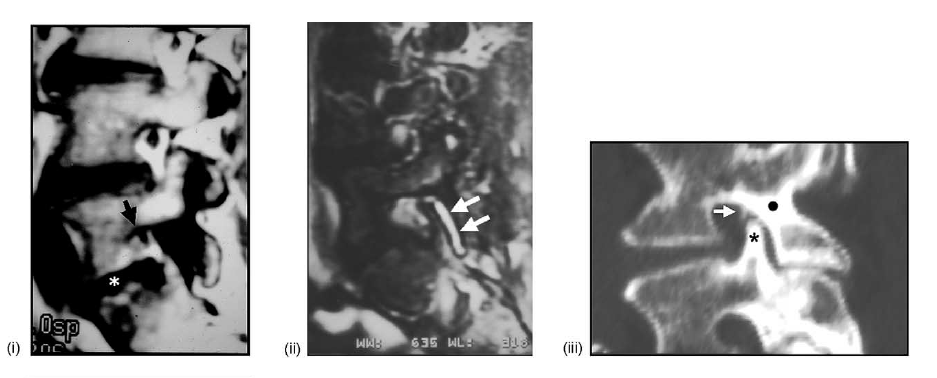

A: anterior, P: posterior. (B) Medical imaging studies: (i) lateral parasagittal CT reconstruction showing the bony structure defining the spinal neural foramen (compare with (A)). (ii) Lateral parasagittal T1-weighted MRI showing the pedicle (white circle) of L5, the superior articular process (white asterisk: zygapophysis) of L5, the inferior articular process (black asterisk: zygapophysis) of L5, the pars interarticularis (white dot) of L5; and a portion of the neurovascular bundle (arrow) exiting-entering the L4-L5 neural foramen. (iii) Lateral parasagittal T2-weighted fat-suppressed MRI showing normal fluid within the superior (arrow) and inferior (arrowhead) recesses of the

L5-S1 posterior spinal facet (zygapophyseal) joint on one side, and the normal high intensity of the dorsal root ganglia (black asterisks) within the neural foramina (compare with (A)).